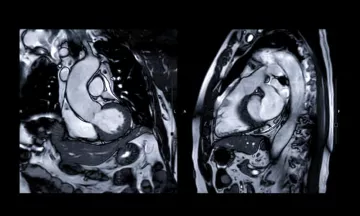

L’Hôpital Privé de Bois-Bernard atteint un nouveau jalon : la 6000 ème IRM cardiaque réalisée !

L’Imagerie Médicale de l’Hôpital Privé de Bois-Bernard est fière d’annoncer la réalisation de sa 2000 ème IRM cardiaque sous stress et 4000ème sans stress*, marquant ainsi un tournant important dans l’offre de soins spécialisés en cardiologie de l’établissement. Ce succès témoigne de l'expertise et de l'engagement de l’hôpital dans la prise en charge des pathologies cardiaques, grâce à l'utilisation d’une technologie de pointe.

IMAGE IRM CARDIAQUE

1000ème IRM cardiaque

La SIMBB a réalisé sa 1000ème  IRM CARDIAQUE sur son plateau technique